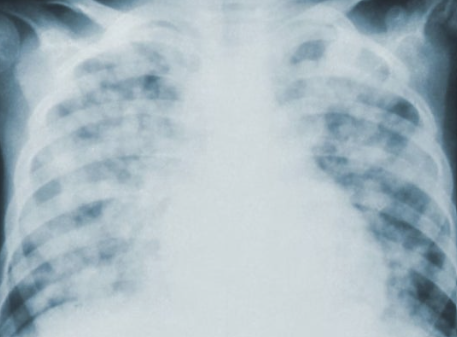

폐기흉 치료는 상태에 따라 달라집니다. 가벼운 경우 산소 공급과 휴식으로 회복될 수 있으며, 심한 경우 흉부관 삽입이나 수술이 필요합니다. 또한, 재발 위험이 높아 예방적 수술을 고려하기도 합니다. 치료는 증상의 정도, 환자의 기저 질환 여부에 따라 맞춤형으로 진행됩니다. 적절한 치료를 통해 합병증을 최소화하고 안전한 회복을 도모할 수 있습니다.

남성이 여성보다 발생률이 높으며, 흡연은 주요 위험 인자로 알려져 있습니다. 특히 고령자나 기저 폐 질환을 가진 환자는 예후가 좋지 않을 수 있어 더욱 관리가 필요합니다. 규칙적인 건강검진과 생활습관 개선은 재발 방지에 도움을 줍니다. 폐 건강을 지키는 생활 관리가 장기적인 예후를 좌우합니다.

폐기흉은 재발 위험이 크므로 꾸준한 관리가 필수입니다. 흡연을 피하고 규칙적인 폐 건강 검진을 받는 것이 중요합니다. 적절한 운동과 생활 습관 개선으로 폐 기능을 유지하면 재발 가능성을 줄일 수 있습니다. 예방적 생활 습관이 폐 건강을 지키는 핵심입니다.